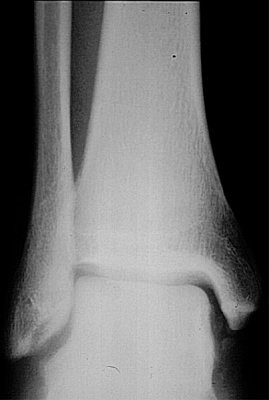

Return to Tillaux Fracture